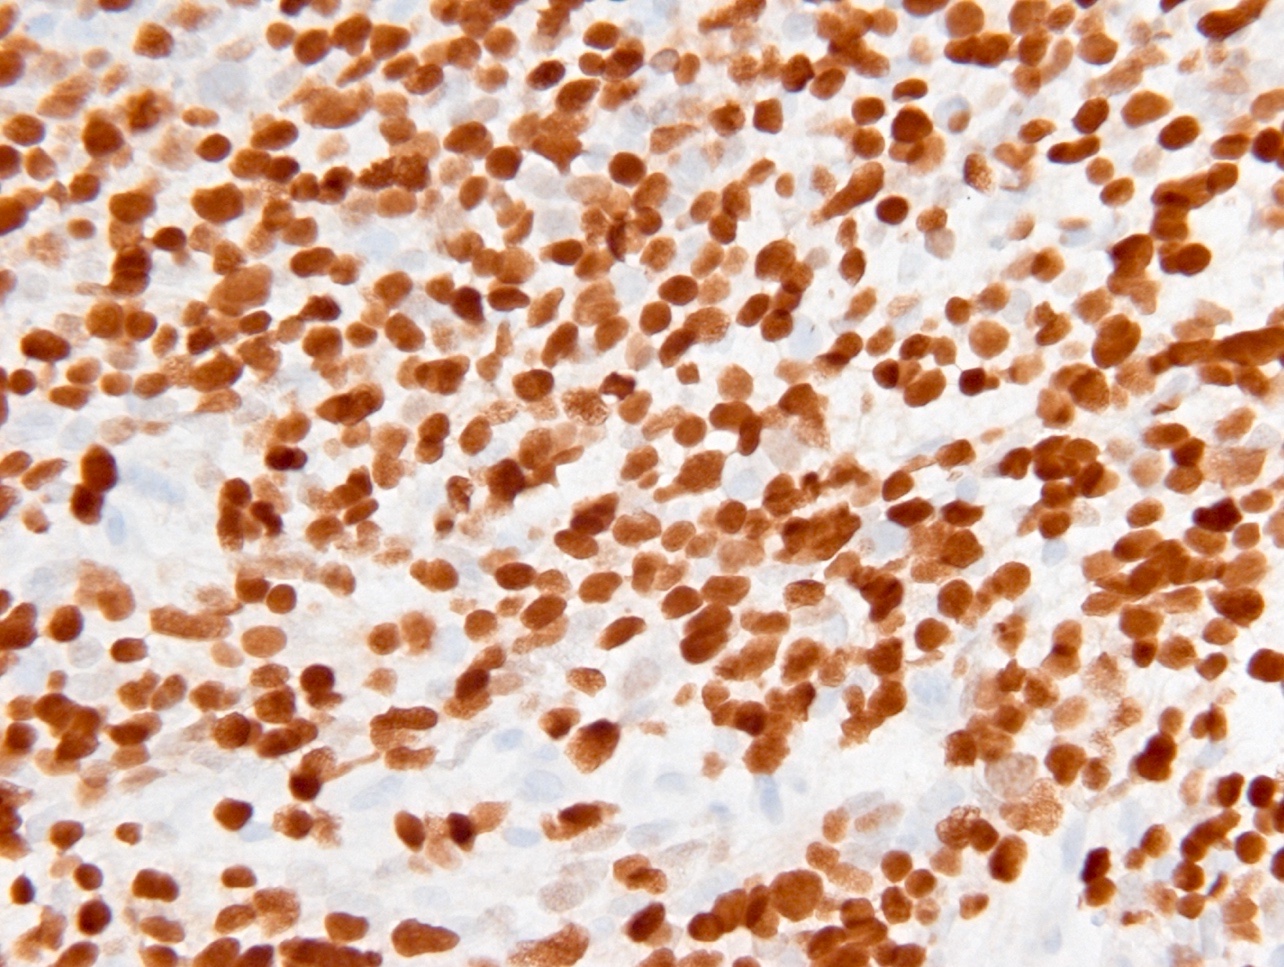

Positive stains

- Olig2

- IDH1

- Marker of infiltrating gliomas, both astrocytic or oligodendroglial (Curr Neurol Neurosci Rep 2013;13:345)

- Recognizes only the most common mutation (IDH1 R132H, which accounts for about 90% of all glioma associated IDH mutations) (Neuro Oncol 2014;16:1478)

- In the absence of immunohistochemical evidence for IDH mutation, other IDH1 / IDH2 mutations must be diagnosed by mutational analysis (Neuro Oncol 2014;16:1478)

- Rare in children < 14 years (Childs Nerv Syst 2011;27:87)

- p53

- Ki67: increasing proliferation index with increasing grade